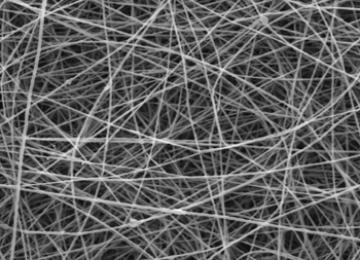

PeopleResearchers at Tehran’s Tarbiat Modares University have developed laboratory scaffolds primarily used in long-term stem cell cultivation. The scaffolds play a vital role in tissue engineering and…